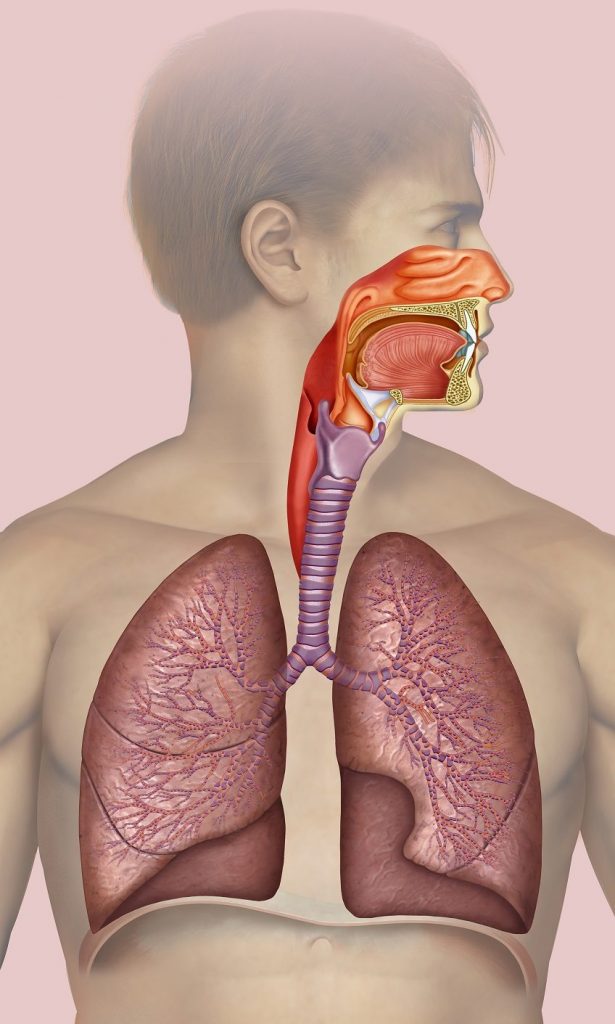

Les corps étrangers peuvent avoir une gravité potentielle, qu’il importe de ne pas négliger. 5 à 10 enfants décèdent par an en France à cause d’un corps étranger dans les voies respiratoires.

Les signes à rechercher sont :

- Une douleur thoracique qui peut être brutale et rythmée par la respiration. Cette douleur peut s’estomper souvent rapidement.

- La dyspnée (trouble respiratoire) d’intensité variable mais sa présence reste inconstante.

- Une toux sèche irritative

Le patient peut également ne présenter aucun symptôme.

Des signes de gravité sont également à rechercher :

Une Polypnée (augmentation de la respiration )≥ 30/min, si le patient devient cyanosé. S’il est victime de malaise. Une hypotension, une tachycardie (battant du cœur augmenté).